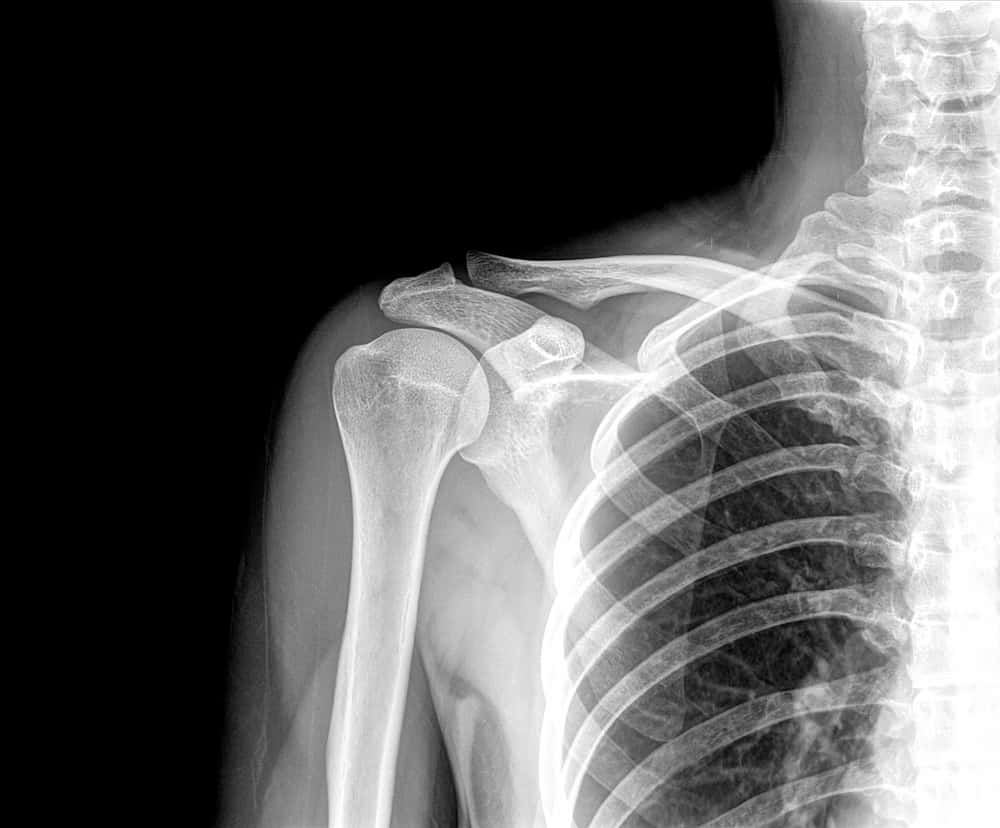

In most cases, osteoarthritis can be suspected or diagnosed through the clinical features (what it looks like and how it behaves), your symptoms (what you tell us about your shoulder) and the clinical assessment (testing the movements etc.). An X-ray of the shoulder is often used to help diagnose osteoarthritis but is not always required.

Why are X-rays/scans not always required?

In a lot of cases, the information we as healthcare professionals can get from asking you questions and testing the shoulder is enough to make a decision. X-rays are a very useful tool as they show you what your shoulder looks like on the inside. However, in some cases what your shoulder looks like on the inside doesn’t really marry up with what your problem might be.

There is growing evidence (experiments and clinical studies) that demonstrate what you see is not always what you get with X-rays and scans and that a lot of the so-called ‘worn out’ or ‘abnormal’ findings are seen commonly in people with no pain, stiffness or symptoms.